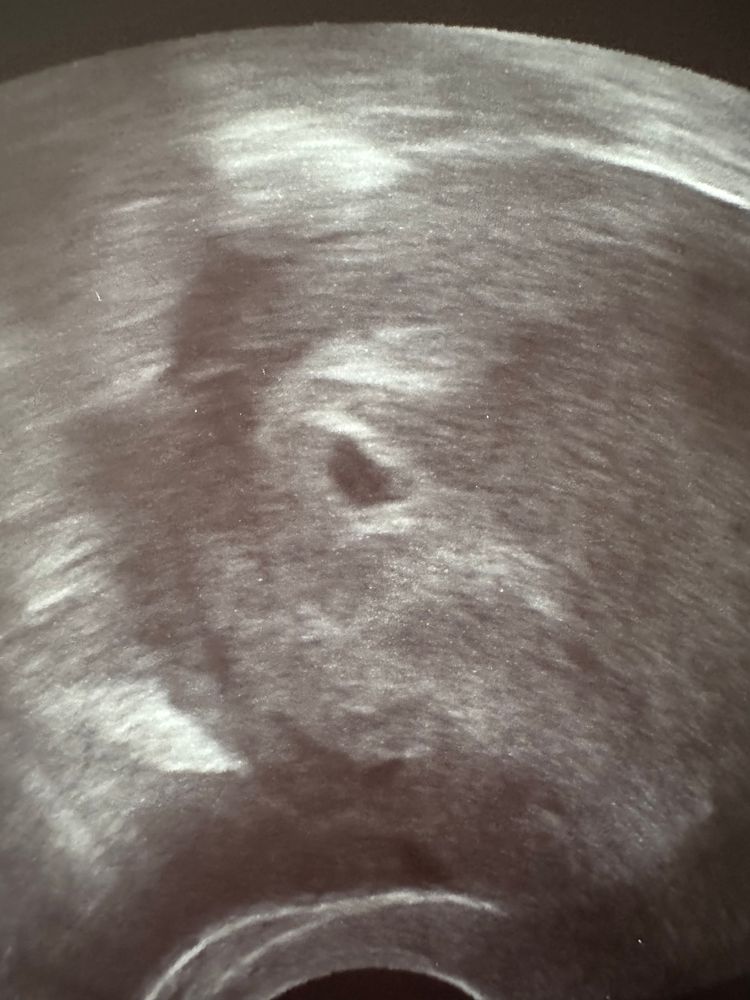

Результаты УЗИДевочки, была сегодня на узи 21 дпп, посмотрели очень быстро, только сам факт наличия пя в матке, а я растерялась, не спросила про жм, теперь переживаю😕 УЗИ в доступности сейчас только такое, за более качественным аппаратом нужно ехать.

Это нормально что пя вытянутое? 10,6 на 5,6.

Мне кажется в правом углу что-то есть или кажется, все фото с замерами. У меня была точно такая же форма на 18дпп, ничего страшного. Про жм тоже сказали что нет, но мне кажется на фото в нижнем углу он был. Рано еще переживать, у вас хгч пониже.